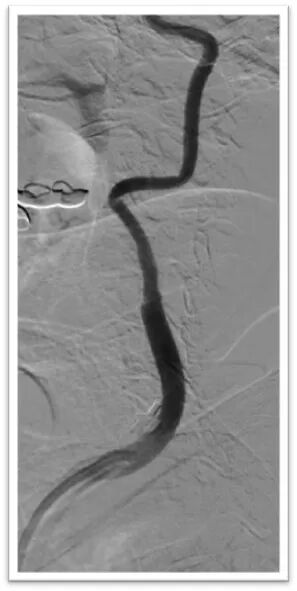

该患者胸主动脉迂曲,主动脉弓呈牛角弓,选择5F 125cm蒸汽塑形后在泥鳅导丝引导下同轴引导6F Neuron Max长鞘顺利置于左侧颈总动脉;